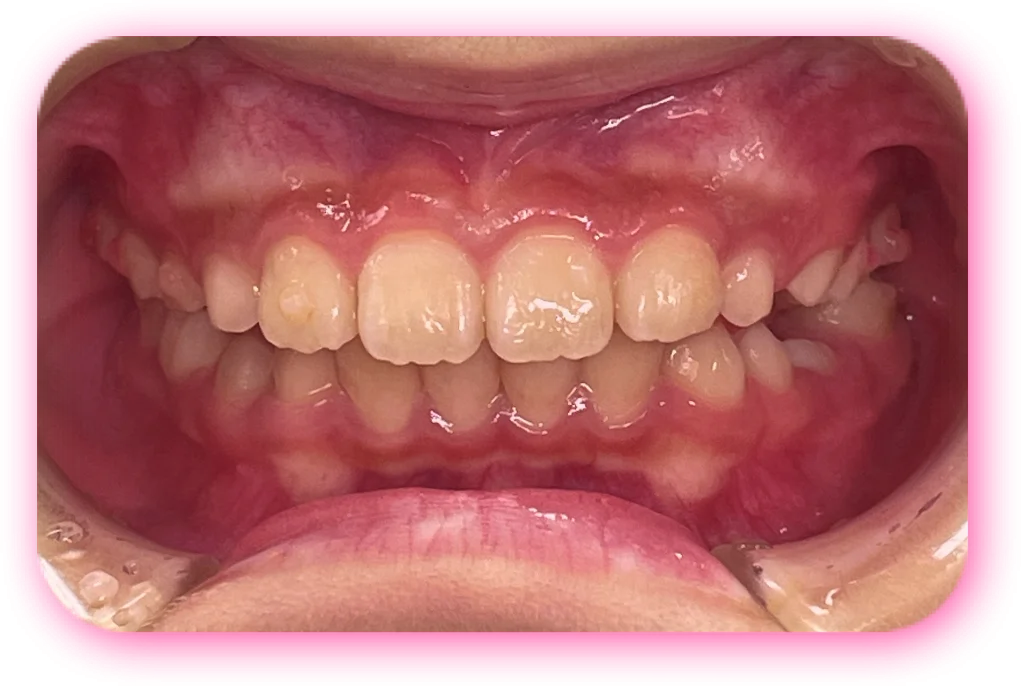

治療後

| 相談内容(主訴) | 出っ歯が気になる |

|---|---|

| 診断結果/行った治療内容 | 上顎前突/インビザライン矯正 |

| 治療期間/回数 | 1.5年/18回 |

| 治療費用 | 80万円 |

| 治療のリスク/副作用 | 歯の移動に伴い歯肉退縮を起こすことがあります/顎関節に症状が出ることがあります |